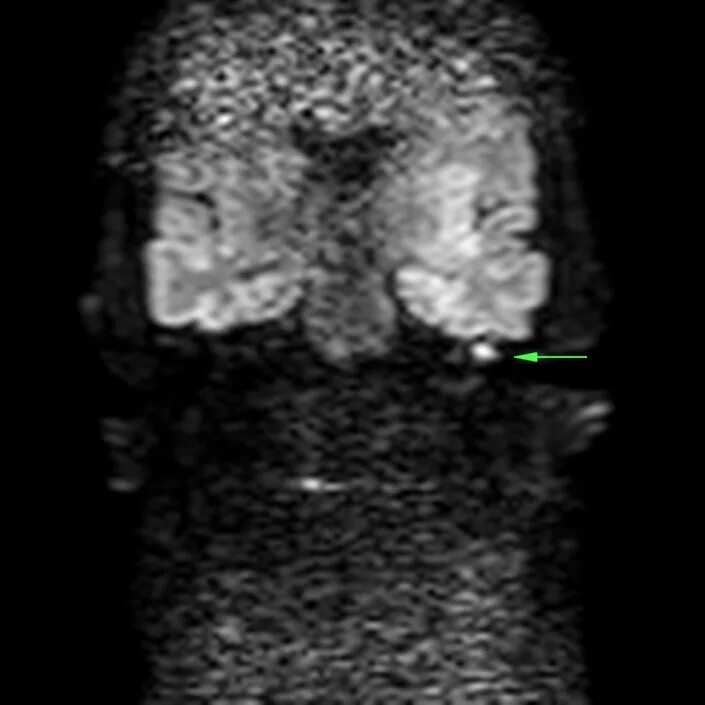

Мрт височных костей в режиме dwi